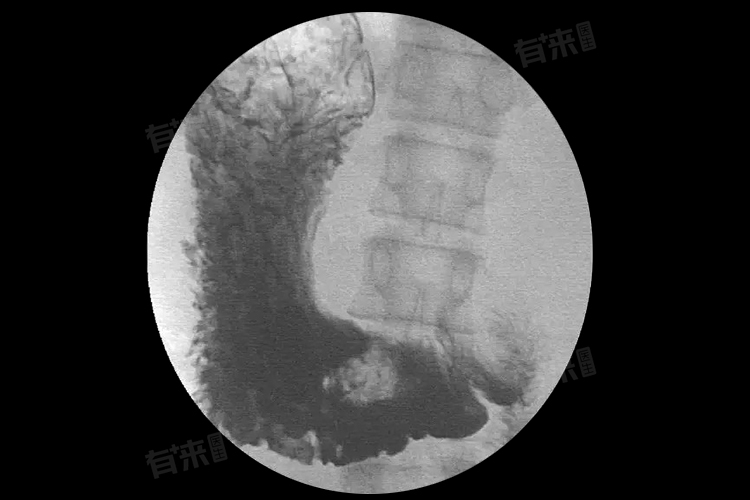

4、胃部疾病:

- 例如胃炎,胃黏膜因炎症刺激,影响了胃的正常蠕动和消化功能,会出现胀满堵塞感。胃溃疡患者,由于胃黏膜受损形成溃疡面,也会干扰胃的正常运作,引发此类症状。